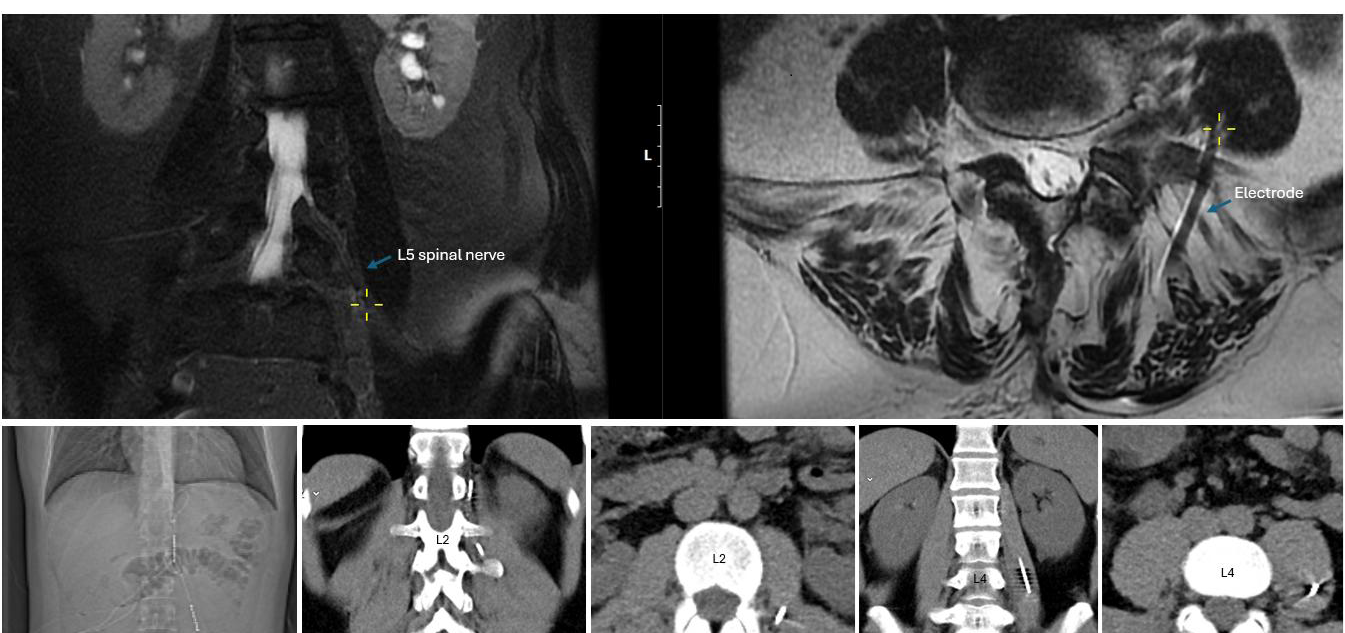

Optimal placement is indicated by low-threshold, clearly visible contractions in the core muscles innervated by the targeted spinal nerve (e.g., quadriceps for L3–L4, tibialis anterior for L5, see Table 1). Ideally, consistent responses at lower current levels across multiple contacts suggest the lead is running parallel and close to the nerve (Figure 4).

Figure 4. Upper panels: Coronal and axial MRI views demonstrating the proximity of the electrode to the left L5 spinal nerve within the psoas compartment in the scoliosis patient shown in Figure 1a. The yellow cross marks the electrode’s entry point into the psoas; the corresponding coronal image illustrates its parallel course and close proximity to the spinal nerve. Lower panels: CT images from another patient with groin pain after herniorrhaphy, implanted with an Xtra4 electrode at the level of L1 and L2 on the left side. The CT scans show the entry site and trajectory of the electrode along the L2 spinal nerve, with the last two images demonstrating its course within the psoas compartment. In both cases, imaging confirms accurate extraforaminal positioning relative to the targeted nerve structure.

Moreover, MRI conditionality remains a concern: most newer SCS systems are MRI-conditional when leads are implanted epidurally, but once implanted in the peripheral nerve region, this use is off-label and lacks formal approval. In one of our patients, an MRI was performed for a new onset of pain at a different spinal level, suspected to be a disc herniation. Imaging demonstrated the proximity of the lead to the L5 nerve (Figure 4). Following conservative therapy, the patient’s pain improved, and the stimulation continued to provide the desired analgesic effect with very low current for effective stimulation at the L5 level.